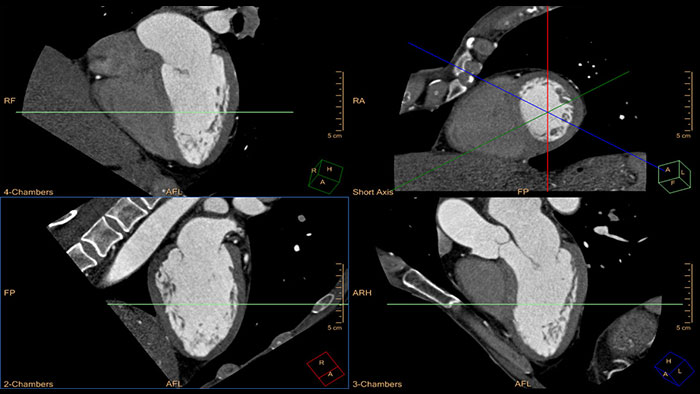

Cardiac Viewer

CT Cardiac Viewer

Quick cardiac visualization

Provides a set of tools for the visualization of one or multiple cardiac phases using original images or MPR\MIP images in axial, coronal, sagittal or dedicated cardiac axes (short axis, horizontal long axis, and vertical long axis).

Benefits

• Automatic removal of the rib-cage structures enables a 3D anatomical Volume Rendering image of the heart and the large blood vessels connected to it.

• The Viewer supports basic measurements as well as basic ventricular functional analysis based on “Area-Length” method to estimate end systolic volume (ESV), end diastolic volume (EDV), cardiac output (CO), and ejection fraction (EF).